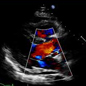

Services Offered: Cardiac Consultation, ECG,  Echocardiography, X-ray, Treadmill Test, Holter study, admissions and Coronary angiogram and angioplasty in reputed hospitals in Chennai